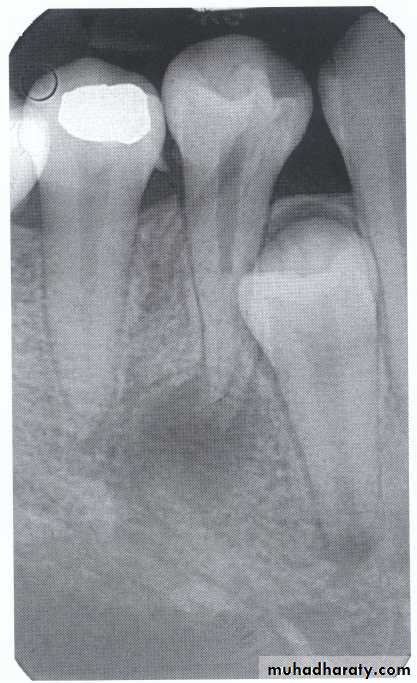

Dilaceration of the crown

specimenX-Ray

Dilacerated root. The apical portion of the root is bent buccally or lingually into the plane of the central ray. Note the halo in the apical region, produced by the PDL

space (arrow).